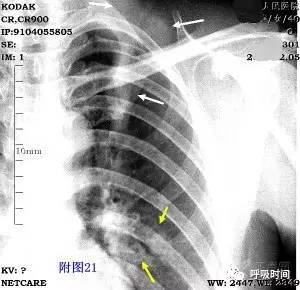

图片

图 23 申请单提供的病情资料:男,44 岁,胸痛 2 天

原诊断:心脏增大。审报告发现,透过增大的「心影」可以看到右侧肺门(蓝箭)及下肺动脉影(黄箭)。

询问病史,患者为食管癌术后。服钡后清楚显示,为胸腔胃(白箭)导致假性心脏增大。